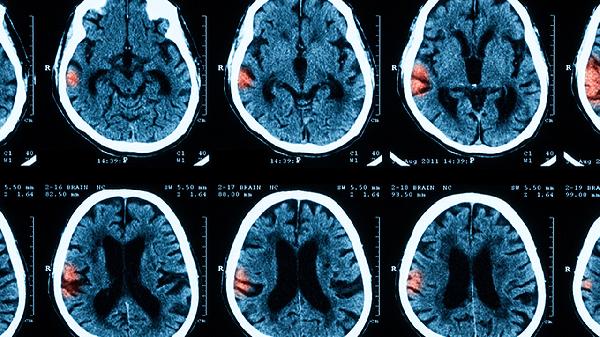

化脓性脑膜炎是由细菌感染引起的脑膜炎症,常见病原体包括肺炎链球菌、脑膜炎奈瑟菌和流感嗜血杆菌。治疗需要及时使用抗生素,如头孢曲松、万古霉素和青霉素,同时辅以对症治疗和预防并发症。化脓性脑膜炎的发病原因多样,感染途径包括呼吸道、血液或邻近器官的感染扩散。预防措施包括接种疫苗、保持个人卫生和避免接触感染源。

化脓性脑膜炎是一种严重的感染性疾病,及时诊断和治疗至关重要。患者一旦出现发热、头痛、呕吐、颈部僵硬等症状,应立即就医,接受抗生素治疗和对症治疗。预防措施包括接种疫苗、保持个人卫生和避免接触感染源,可以有效降低感染风险。通过早期发现和及时治疗,大多数患者可以完全康复,避免严重并发症的发生。